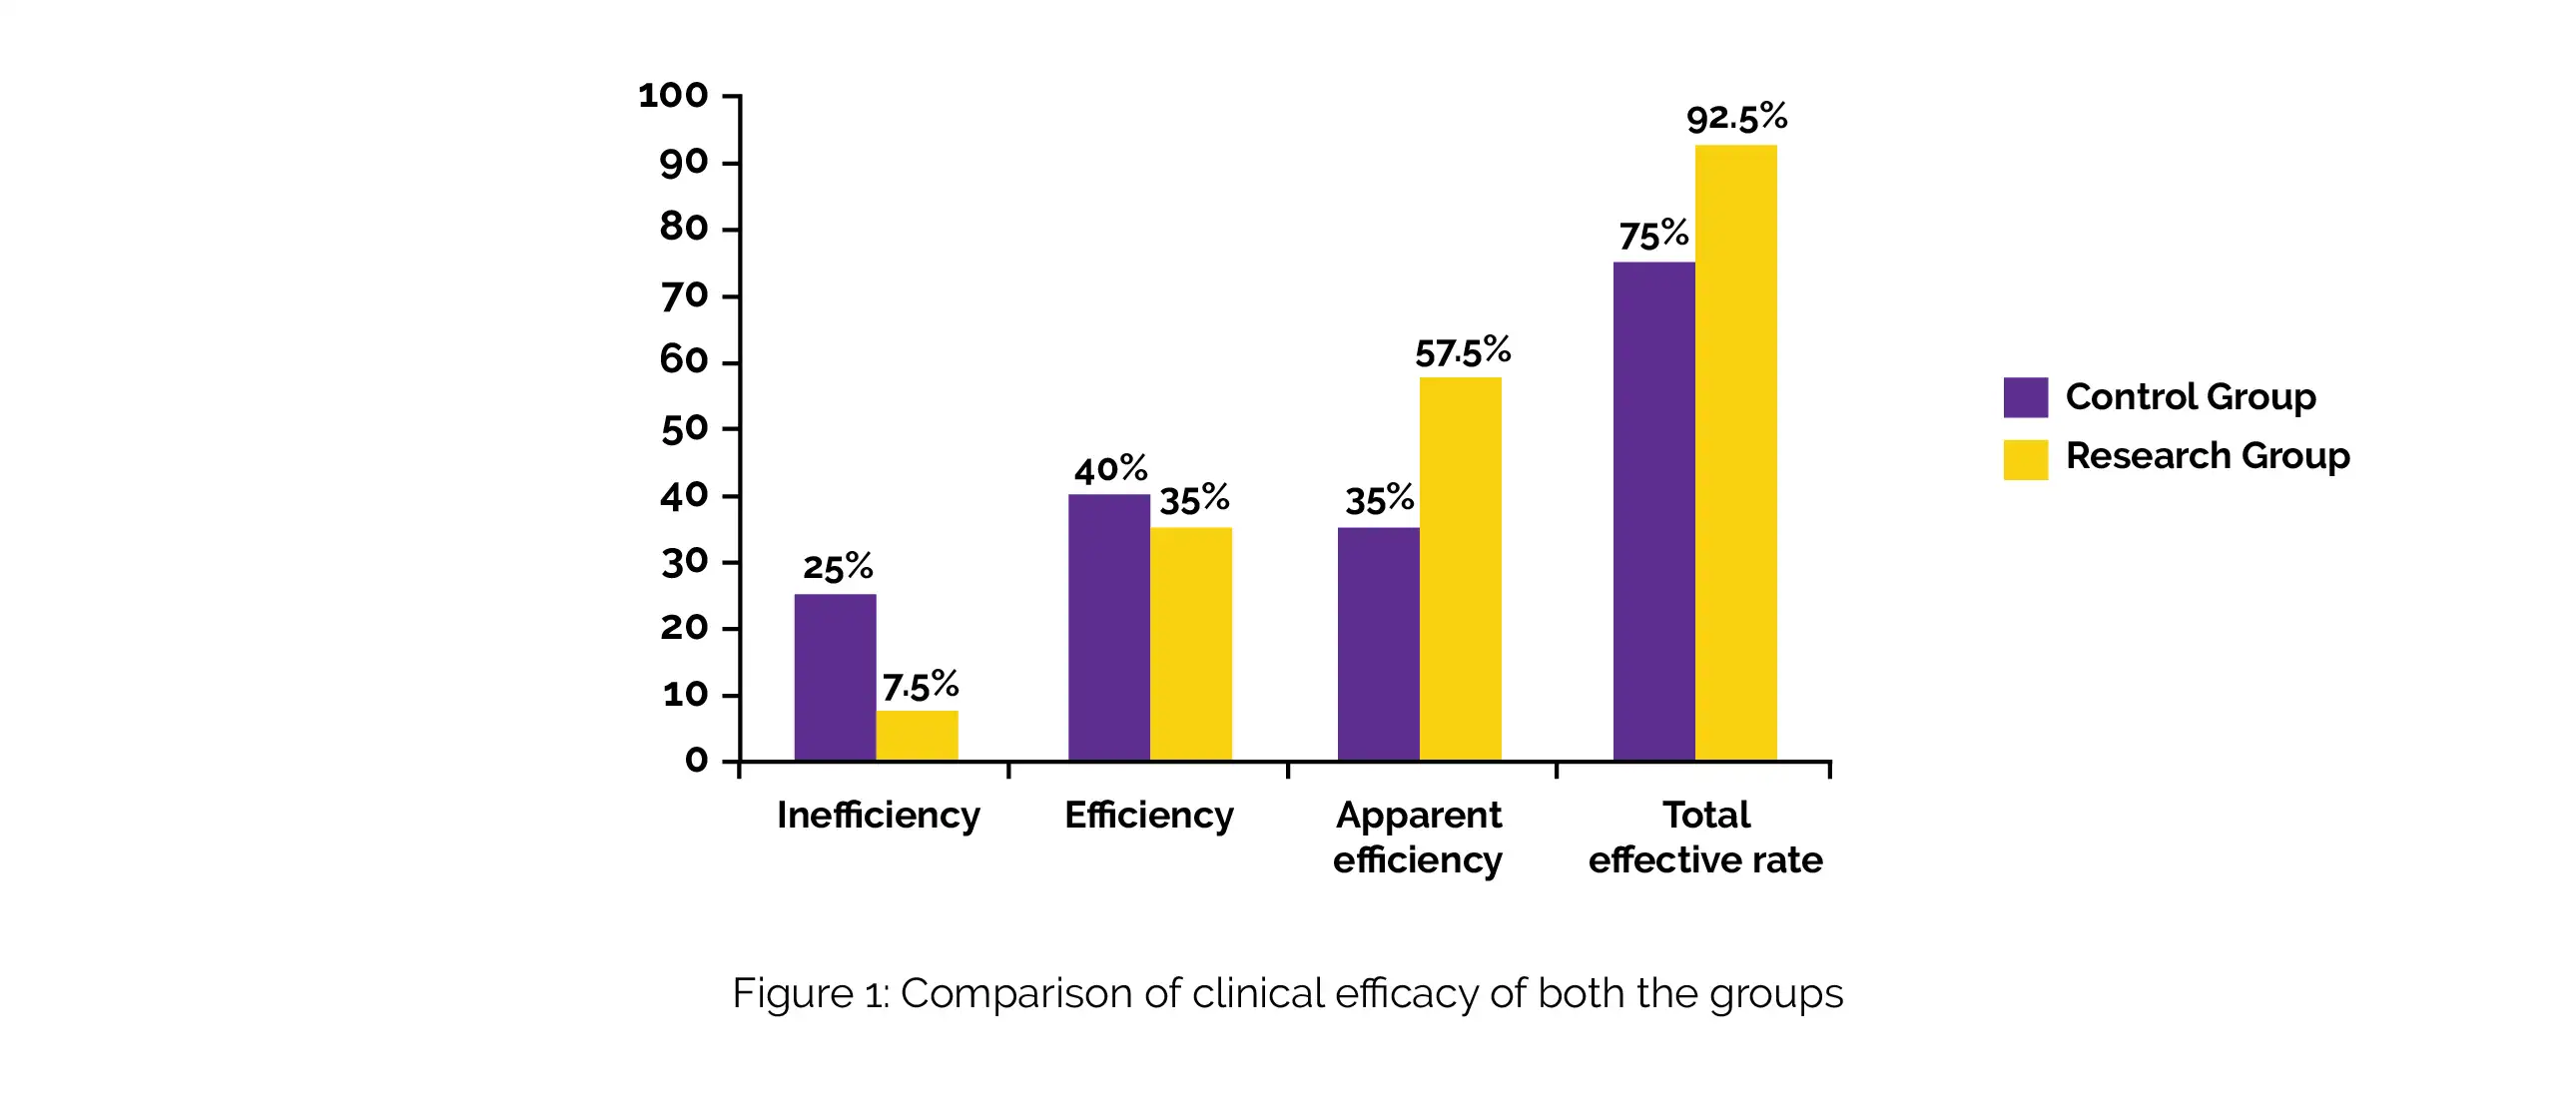

In comparison to Rupatadine fumarate alone (10 cases of inefficient, 16 cases of efficient, and 14 cases of markedly efficient), Rupatadine fumarate + Acupoint application was associated with remarkably greater effectiveness (3 cases of inefficient, 14 cases of efficient, and 23 cases of markedly efficient), as shown in Figure 1: